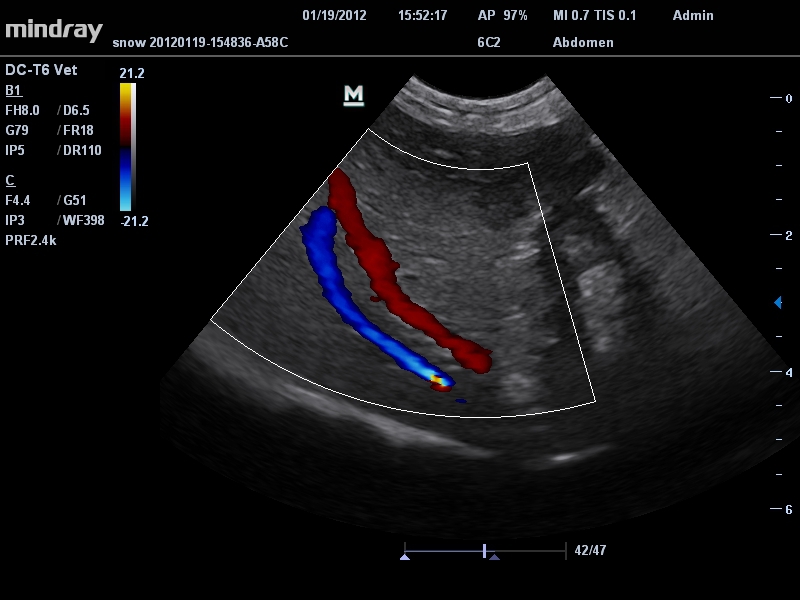

Цветовой допплер:

Да

Импульсно-волновой допплер:

Ветеринария: